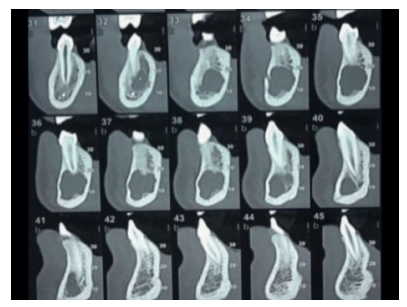

Se solicitó como prueba complementaria un CBCT mandibular. En los cortes panorámico, axiales y ortorradiales, se corroboró la presencia de lesión radiotransparente delimitada de contorno algo irregular y que no provocaba expansión de corticales (Figuras 1-4).

Radiográficamente presenta una imagen radiotransparente unilocular mostrando un festón en el área interradicular de los dientes afectos y de zonas edéntulas, pudiendo incluir sus raíces en la lesión, pero sin rizolisis; aunque en el sector anterior acostumbra a tener forma ovalada. Es radiotransparente con bordes irregulares, pero bien definidos. La expansión ósea sin perforación de corticales serían criterios asociados a esta lesión benigna, erosionando el endostio y por tanto adelgazando la cortical 2,3,5,6 .